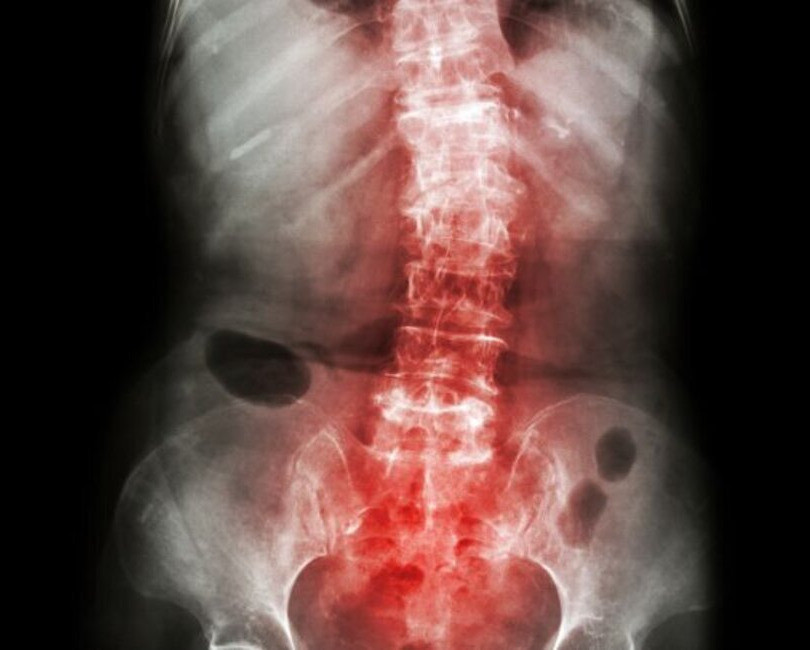

Spondylitis, particularly Ankylosing Spondylitis (AS), is a type of arthritis that primarily affects the spine, leading to severe, chronic pain and discomfort. It can also cause inflammation in other body parts, including the eyes, heart, and lungs. The exact cause of spondylitis is unknown, but genetics play a significant role, with the HLA-B27 gene being a common marker in patients.

Symptoms of Spondylitis

Common symptoms of spondylitis include:

- Chronic pain and stiffness in the lower back and hips, especially in the morning or after periods of inactivity.

- In severe cases, the formation of new bone can cause parts of the spine to fuse, leading to a stooped posture.